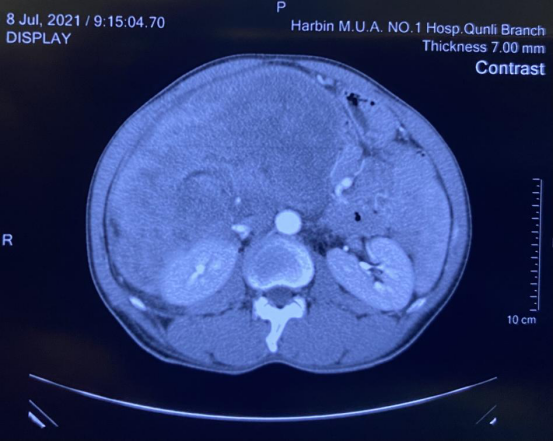

来自鸡西市的洪某是个瘦弱的人,但却有一个大大的“啤酒肚”,在当地医院检查这个啤酒肚原来是肝内多发占位,腹腔巨大囊性占位造成的。洪某赶忙来到ac米兰官网中文网站一院群力院区普外一科找到朱安龙教授,在完善相关检查后,朱安龙诊断洪某腹膜后长了一个巨大的肿瘤,肿瘤几乎填满了他的腹腔,右侧的肠管已经被挤压到了左侧,右侧肾脏也被牢牢地压在后方。

腹腔分为腹腔和腹膜后,没有腹膜覆盖的后方位置就叫腹膜后。朱安龙介绍,腹膜后肿瘤的手术难度比腹腔肿瘤难得多。腹腔巨大肿瘤就像是一个带根的西瓜,手术时一般只需要斩断“瓜蒂”即可。但是腹膜后肿瘤就完全不同,首先腹膜后在人体的深部,原本手术难度就很高,而这次的肿块占据了整个腹膜后空间,与多脏器关系密切,包括肝脏、肾脏、结肠、十二指肠等,并包绕了下腔静脉,肿瘤更是覆盖住了整个右肾区域,这个肿瘤的切除过程,相当于把腹部主要血管全部解剖一遍,难度之大极其考验术者的技术和经验。